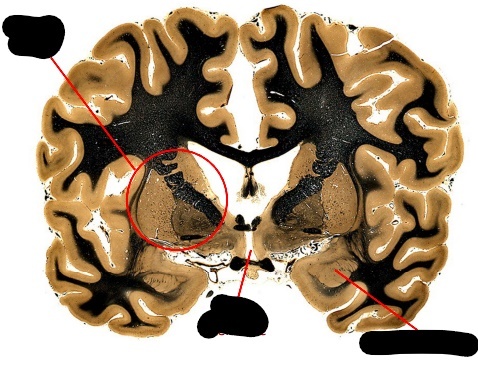

what is the massa intermedia?

label, note important features